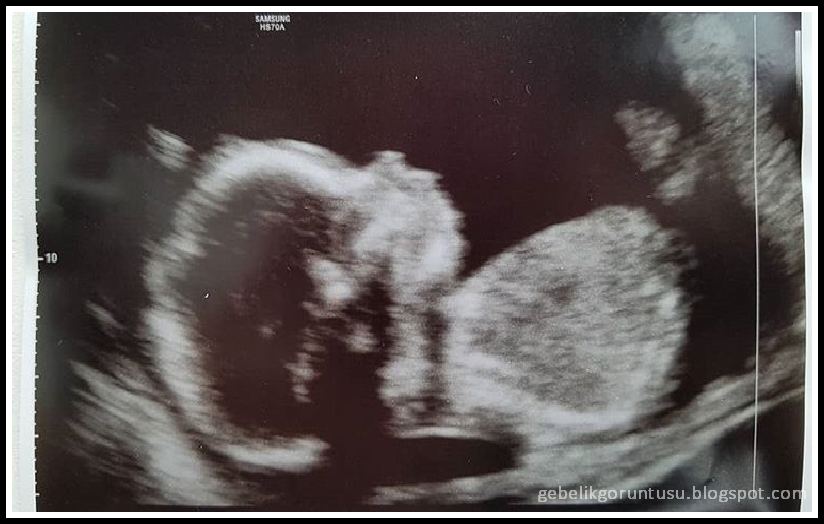

19 haftalık gebelik anne karnı: Anne karnı daha da büyüdü. (Aşağıdan 19 haftalık anne karnı fotosuna bakabilirsiniz.)